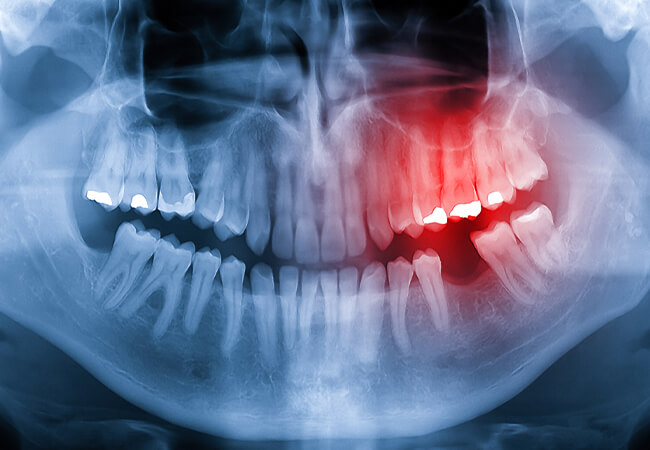

歯科口腔外科での身近な外来手術に「親知らずの抜歯」があります。「親知らず」は、奥歯の一番奥に生えてくる永久歯で、「第3大臼歯(だいさんだいきゅうし)」とも呼ばれています。一般的に生えてくる時期は10代後半から20代前半ですが、まれに30~40歳頃に生えてくる場合もあります。はじめから「親知らず」がない方や上下左右の4本が揃っていない方など、個人差があります。また、まっすぐに生えてくるとは限らず、斜めに生えたり、埋まったままだったりすることもあります。

「親知らず」は、必ず抜かなければならないというものではなく、痛みがない場合や周りの歯や歯列に影響がない場合は、無理に抜く必要はありません。抜歯が必要な症状としては、「歯ぐき(歯肉)の腫れや痛みを繰り返している」「頻繁に食べ物がつまる」「手前の歯や『親知らず』がむし歯になっている」「『親知らず』が他の病気の原因になっている」などが挙げられます。

抜歯は、周囲の神経や太い血管の確認が必須となります。歯科用CTで「親知らず」を立体的に把握し、神経や血管の位置を考慮しながら行います。